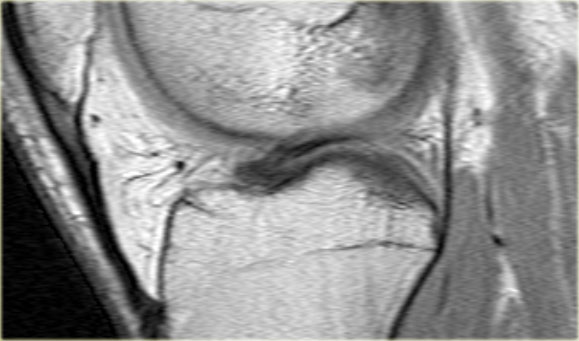

Cùng ca bệnh trên với hình ảnh mặt phẳng sagittal.

Lưu ý phần bị rách của sụn chêm chạy ra phía trước qua hố gian lồi cầu (các mũi tên)

- Thông thường chỉ có hai cấu trúc chạy trong hố gian lồi cầu. Ở đây chúng ta thấy dây chằng chéo sau bình thường.

- Dây chằng chéo trước bình thường.

- Phần bị rách của sừng sau như là ‘cấu trúc thứ ba’

trong hố gian lồi cầu. - Phần bị rách chạy ra phía trước.

- Phần bị rách nhập vào sừng trước và giả tạo hình ảnh rách dọc ở sừng trước.

Lưu ý phần còn lại nhỏ của sừng sau.